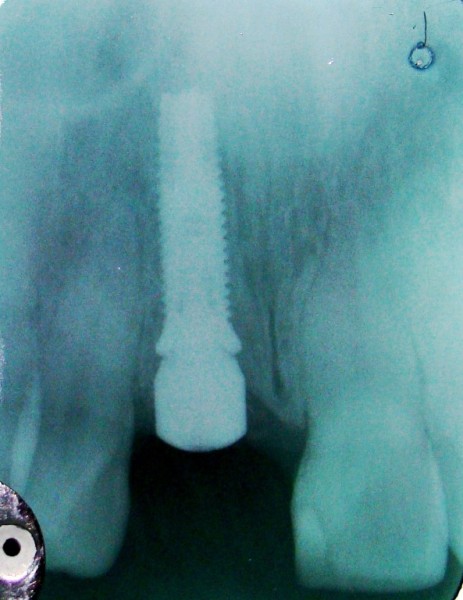

• Titanium root shaped implants are placed into the jaw.  The bone grows to the surface resulting in integration (fusion of the jawbone directly to the implant).  Teeth can then be restored on top of the integrated implant(s).

Immediate Molar Implant